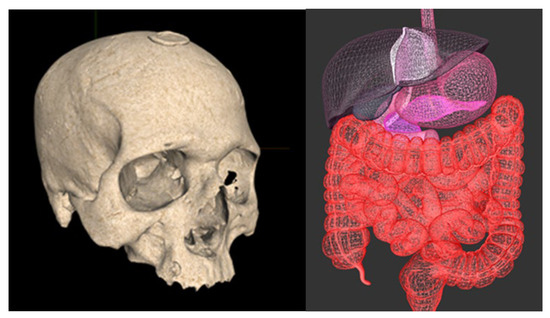

With reference to Figure 13, we show a human skull of a catholic saint that is rendered in the solid mode and a human abdomen. The skull model represents a skull (cranium) of a catholic relict—it is created by a professional 3D scanner and is a part of the Interactive Virtual Shrine (IVS) project [43], which provides anthropological and religious aspects of catholic relicts. Its vertex attributes are position, normal, and texture coordinates, and it is rendered in the solid mode. The abdomen model is created by a DCC tool; its vertex attributes are position, normal, and color; and it is rendered in the wire-frame mode without culling back triangles.

Figure 13. Rendering triangle meshes with VanityX. The relict on the left side is stamped with the papal seal. It is provided by courtesy of Reverend Marijan Jelenić, the catholic church in Vodnjan, Croatia. On the right, we render a human abdomen.